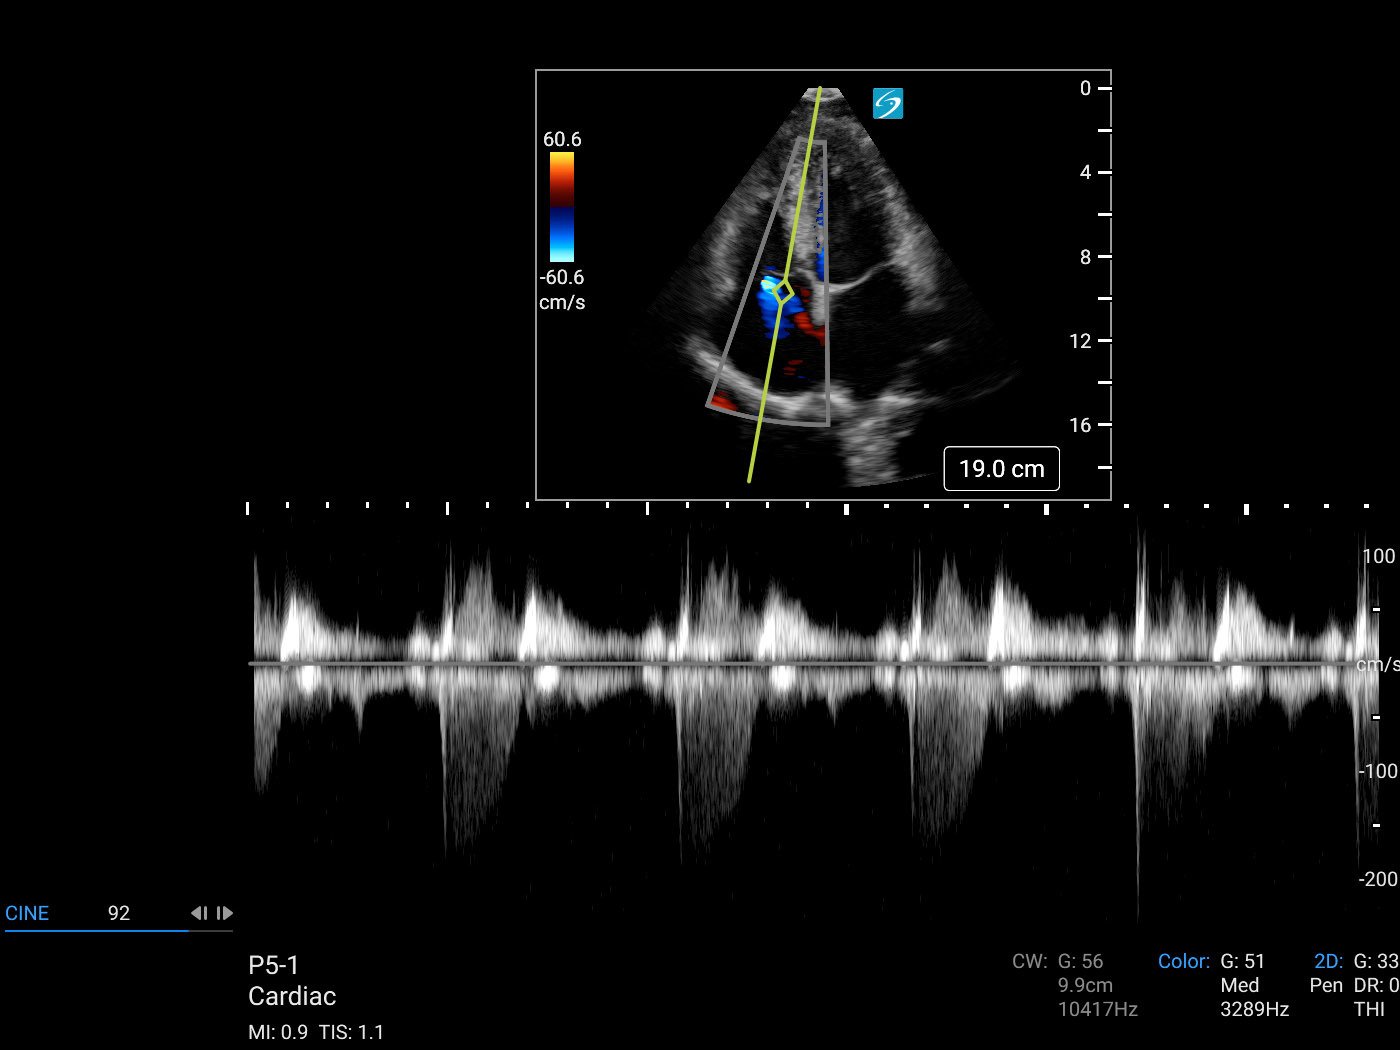

Cardiac 2 Tricuspid Regurgitant Jet CW Line (Sonosite PX P5-1) Image